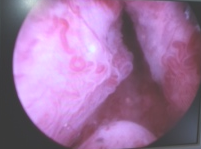

Antes de operar con láser verde.

Intervención con láser verde en próstata, el adenoma de la foto anterior ha desaparecido.